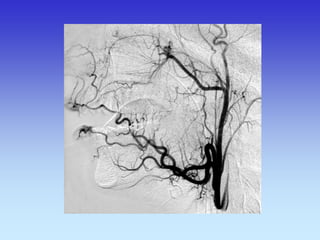

METODE PRIKAZA KRVNIH ŽILA

•UZ-DOPPLER

•DSA

•CTA

•MRA

VASKULARNA OPSKRBA WILLIS-ijev prsten